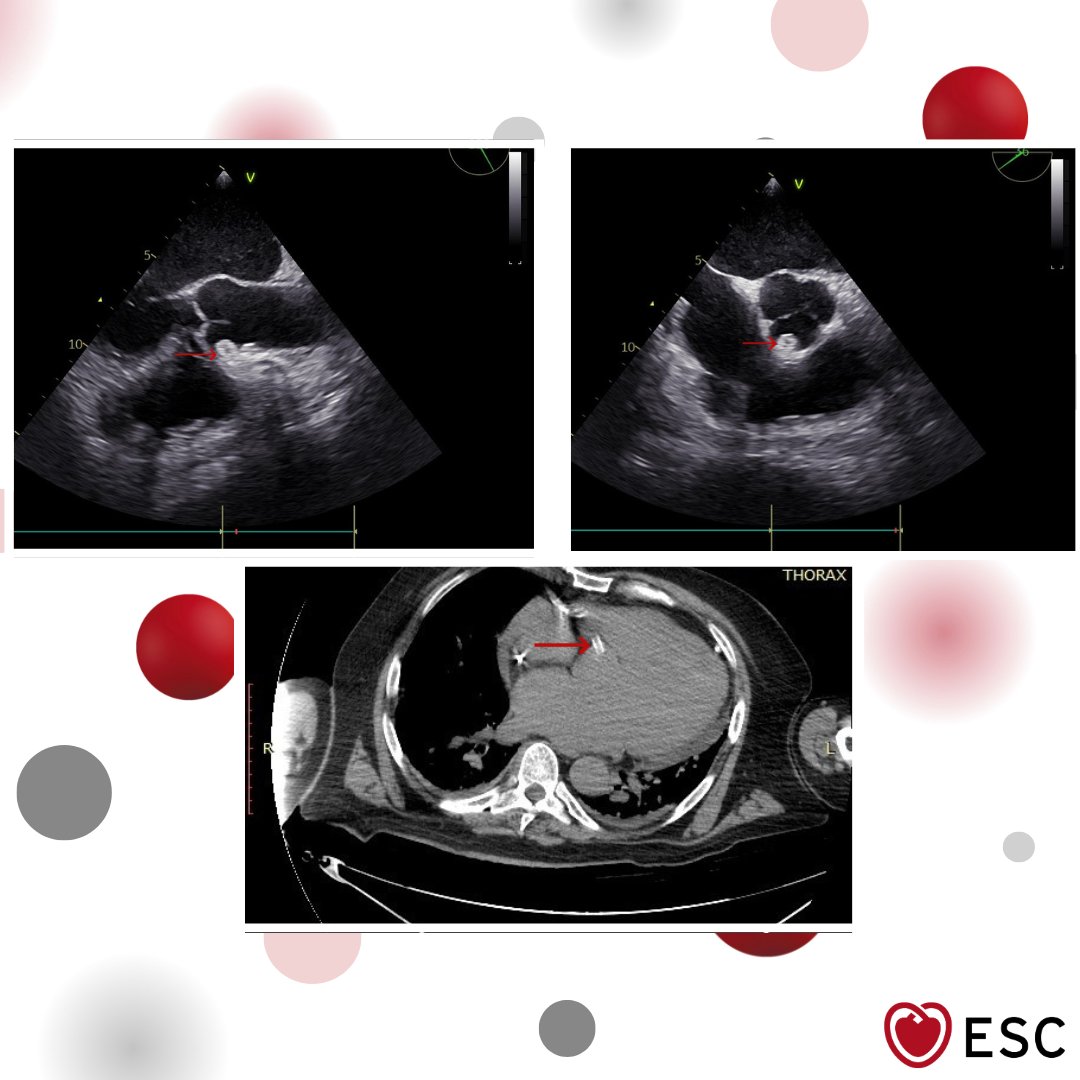

#ImageoftheWeek This #Quiz was submitted by Leila Bigdelu and Ossama Maadarani from the Cardiovascular Medicine Division, Vascular Surgery Research Center, Mashhad University of Medical Sciences, Mashhad, 🇮🇷 ☑️shorturl.at/sdVxi What is your diagnosis? @EACVIPresident

echo_stepbystep's tweet image. #ImageoftheWeek This #Quiz was submitted by Leila Bigdelu and Ossama Maadarani from the Cardiovascular Medicine Division, Vascular Surgery Research Center, Mashhad University of Medical Sciences, Mashhad, 🇮🇷

☑️shorturl.at/sdVxi

What is your diagnosis?